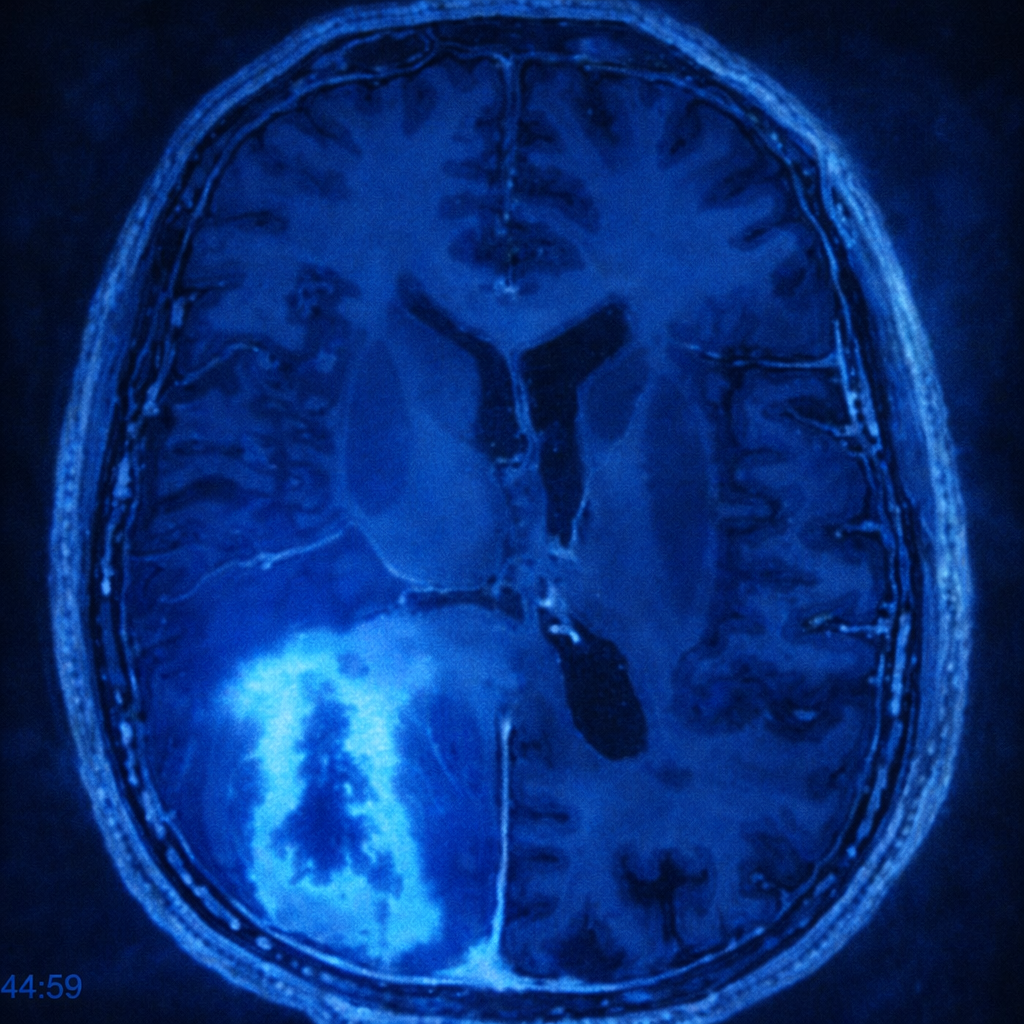

Glioblastoma multiforme (GBM)

Es el tumor cerebral maligno más frecuente y agresivo en adultos. Se origina en las células gliales del cerebro, encargadas de sostener y proteger las neuronas. Este tipo de cáncer se caracteriza por su rápido crecimiento y su capacidad de infiltrarse en el tejido cerebral sano, lo que dificulta su tratamiento. Aunque representa un desafío terapéutico, existen opciones que pueden mejorar la calidad de vida y prolongar la supervivencia.

• Resonancia magnética (RM): principal herramienta para localizar el tumor y evaluar su extensión.